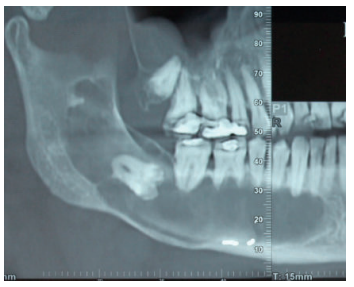

Acudió a servicio de cirugía oral, derivado por su odontólogo, un paciente varón de 65 años sin antecedentes médicos de interés, tras comprobar un importante crecimiento de una imagen radiotransparente respecto a última radiografía de hacía 5 años. El paciente no refirió sintomatología asociada. A la exploración extraoral no se apreció ningún tipo de deformidad ni afectación ganglionar. A la exploración intraoral pese a que se constató la integridad de las corticales, las cuales no estaban abombadas, sí que se pudo apreciar a la palpación un signo positivo de Dupuytren o de “Ping-Pong”. Además se constató una falta de afectación de los dientes del cuarto cuadrante que no presentaban movilidad y tenían una vitalidad positiva (Figura 1). Como complemento a la exploración clínica se solicitó un estudio mediante TAC, donde se apreció la extensión de una lesión radiotransparente que afectaba a rama y cuerpo mandibular derecho. (Figuras 2 y 3).

Dicha sensación de parestesia todavía perduraba en la última revisión realizada a los seis meses después de la intervención, momento en que se realizó una nueva radiografía panorámica. En ella se aprecia una buena osificación del gran defecto remanente (Figura 14).